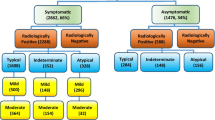

In order to select chest CT scans for analysis, our exclusion criteria were RT-PCR for SARS-CoV-2 that was ultimately determined to be negative. Figure 1 shows the patient's enrollment flowchart.

Patient demographics, clinical and laboratory findings

Demographics, clinical and laboratory findings are reported in Table 1. The analysis included 98 patients (median age, 61 years old; range 23–91 years old), 39/98 (39.80%) were females. Five patients were excluded for negative result at RT-PCR test (Fig. 1). No symptoms (fever, cough, respiratory failure, dyspnea or other including arthralgia, diarrhea, leukopenia, nausea), no comorbidities (hypertension, diabetes, neurological, cardiovascular, oncological, pulmonary) determined differences statistically significant in terms of patient outcome (Table 1). Among admission laboratory findings, SpO2, high sensitivity C-reactive protein (HS CRP), leukocyte count, neutrophils percentage value, lactate dehydrogenase value (LDH), d-dimer, troponin, creatinine and azotemia, ALT, AST and bilirubin values showed differences statistically significant compared to patient outcome (Table 1). SpO2 was significantly lower in patients hospitalized in critical conditions or died while age, HS CRP, leukocyte count, neutrophils percentage value, LDH, d-dimer, troponin, creatinine and azotemia, ALT, AST and bilirubin values were significantly higher (Table 1).

Automatic segmentation on CT images based on Hounsfield unit was performed on 74 patients because the AI tool was not able to segment automatically GGO, consolidations or emphysema in 24/98 (24.5%) cases (Fig. 1). Therefore, radiological severity visual score on CT for COVID-19 disease was provided for these 74 patients.